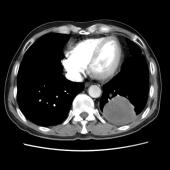

[影像描述]

左肺下叶可见高密度肿块影,边界清晰,边缘不规则,左肺下叶支气管局部截断,增强后病灶边缘轻度强化,中心未见明显强化;左侧胸腔内可见液性密度影;纵隔内未见明确肿大淋巴结影。

(左下叶)肺肉瘤样癌(巨细胞癌),伴大片坏死

肺肉瘤样癌是一种少见的非小细胞肺癌,WHO将其分为5个亚型:多形性癌、梭形细胞癌、具巨细胞癌、癌肉瘤和肺肉瘤。主要见于老年患者,男多于女,临床症状与肿瘤生长部位及侵犯周围组织的情况有关,中央型较易侵犯支气管,症状往往出现较早。CT多表现为肺内单发肿块影,最大径一般大于5cm,周围型多于中央型,可跨叶生长;边缘光滑或清晰;毛刺征及胸膜牵拉症少见;坏死、空腔及分叶、支气管截断多见,坏死边界不清,可见坏死内强化灶,肺门及纵隔淋巴结转移多为环形强化。需要鉴别以下几种疾病:肺结核球呈圆形或类圆形,多数密度不均匀,周边或中央常可见钙化,病灶中心有时可见小空洞。病灶边缘清楚,部分边缘可呈浅分叶状,少数可见毛刺征或胸膜凹陷征,周围常可见卫星灶。增强检查病灶不强化或仅轻度强化。周围型错构瘤直径多在2.5cm以下,瘤体内可见斑点状或爆米花状钙化,部分病变有脂肪密度,多数病变边缘清楚、光滑,CT增强大多数病灶无明显强化。肺炎性假瘤呈圆形或类圆形高密度影,密度较均匀,边缘多清楚而光滑,少数可呈毛刺样改变,增强检查大多数肿块较显著均匀强化。